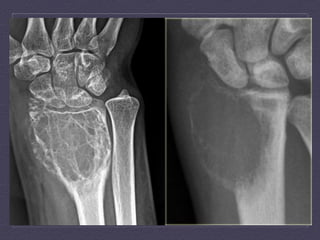

Giant  Cell  Tumor     Benign,  metaepiphysis  of  long  bones       Early  adulthood  (  20-­‐  50  y.o)     Single  lesions  (knee,  distal  radius,  sacrum)     X-­‐Ray  and  CT  :  occurs  only  with  a    closed  epiphyseal   plate,  ar:cular  surface,  well  defined  with  non-­‐ sclero:c  margin,  periosteal  reac:on  (10-­‐30%  cases),   no  calcifica:on     MRI:  low  signal  in  T1WI  and  T2WI     Angiography:  hypervascular  tumor  with  the  rest   being  hipo/avascular

ENCHONDROMA  VS  LOW  GRADE  CHONDROSARCOMA